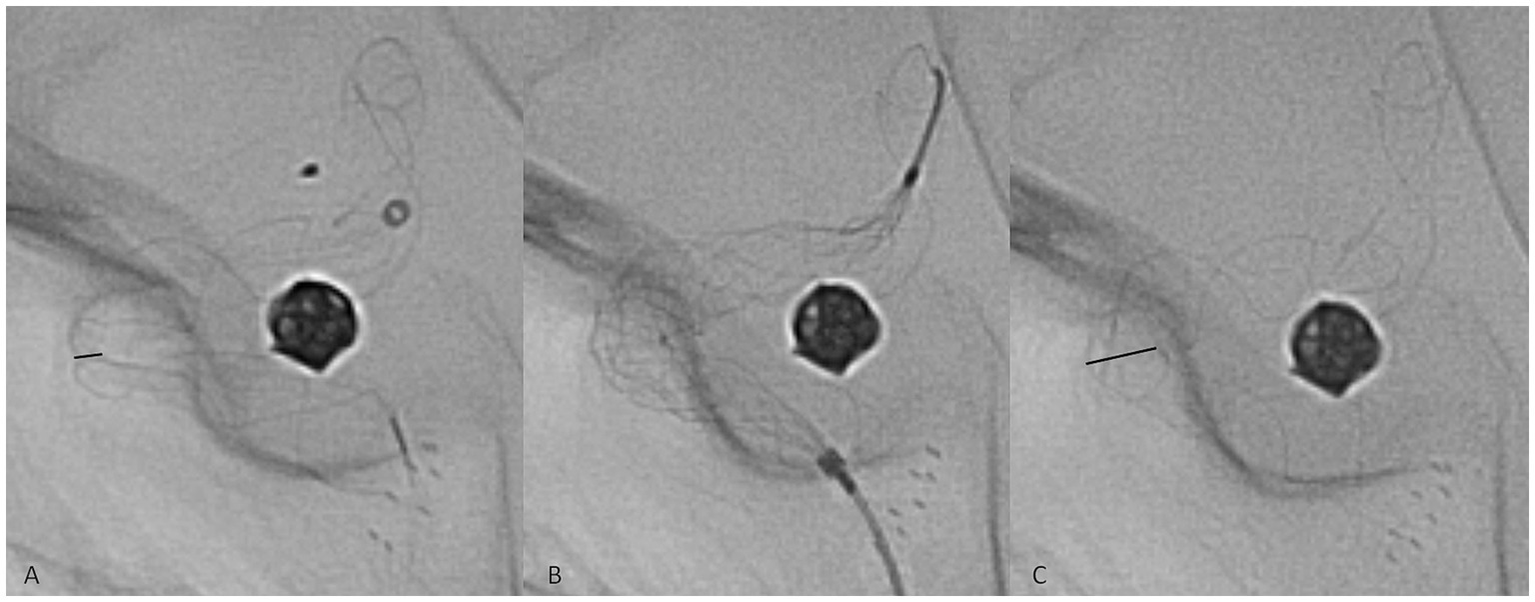

No immediate peri- or postprocedural clinical complications associated with therapy were observed. The technical complication rate associated with device delivery was 5.1%: in seven cases, implant deformation during the procedure was observed, with inadequate wall apposition. In all of these cases, angioplasty was performed to remedy the issue with a Comaneci temporary stent (Rapid Medical, Israel), which was passed through the 0.027″ stent delivery microcatheter (Figure 2). The temporary stent was opened at the deformation site until satisfactory results were achieved. No thromboembolic or hemorrhagic complications associated with the angioplasty were observed. Late clinical manifestations were observed several days after prasugrel discontinuation at the 1-year follow-up in two patients with ISS. The patients reported contralateral weakness of the limbs, and one of them had accompanying contralateral facial palsy and transitory aphasia. DAPT was again prescribed, and the symptoms spontaneously resolved in both patients within several days.

Figure 2

Representative case of a technical complication during flow diverter stent delivery. The twisting of the implant in the middle zone of a curve was observed (A, black line, representing the diameter of the twisted segment of the implant). A Comaneci temporary stent (B) was passed through the Phenom 27 microcatheter, and the expansion of the Comaneci stent inside the twist opened the p64 completely (C, black line).